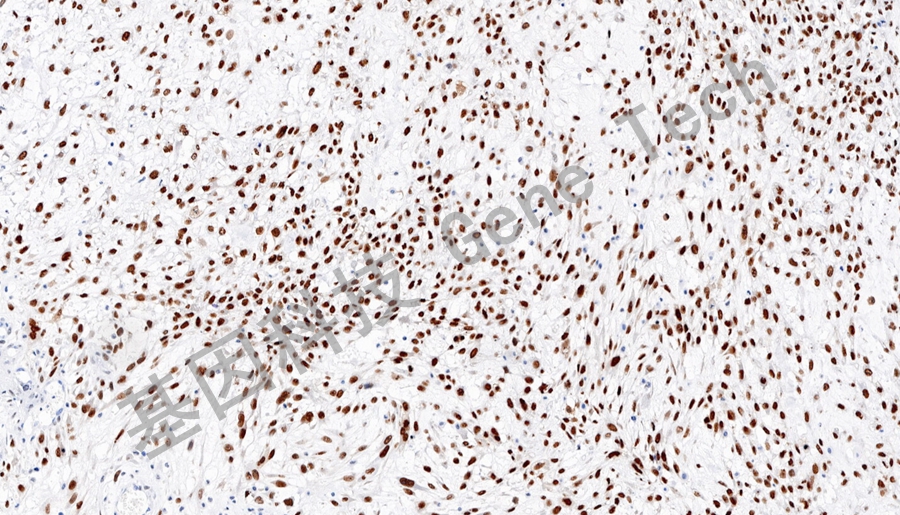

RUNX2抗体试剂(免疫组织化学法)

| 预处理:高pH热修复 | 阳性部位:细胞核 | 阳性对照:骨肉瘤 |

| 骨肉瘤石蜡切片,用 RUNX2(GT2602)染色,细胞核阳性,DAB 显色。 | ||